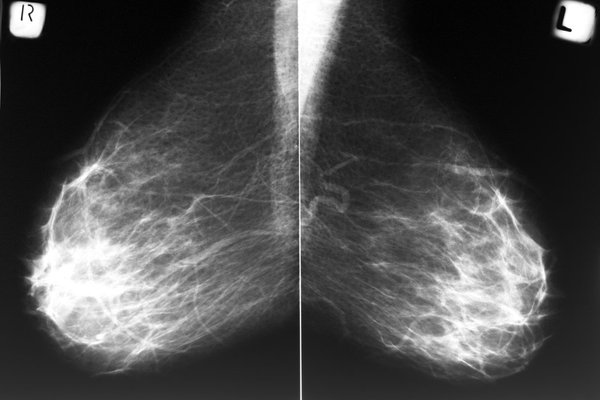

Breast density is the measurement of fibrous and glandular tissue in your breast compared to fatty tissue. The more fibrous and glandular tissue you have, the more difficult it will be to detect cancer on a mammogram.

In addition, dense breasts make it difficult to see abnormal changes. Glandular tissue and cancerous masses both appear white on a mammogram, making it hard to tell them apart. Unlike dense breasts, fatty tissue appears as mostly black on a mammogram, making it easier to see tumors.